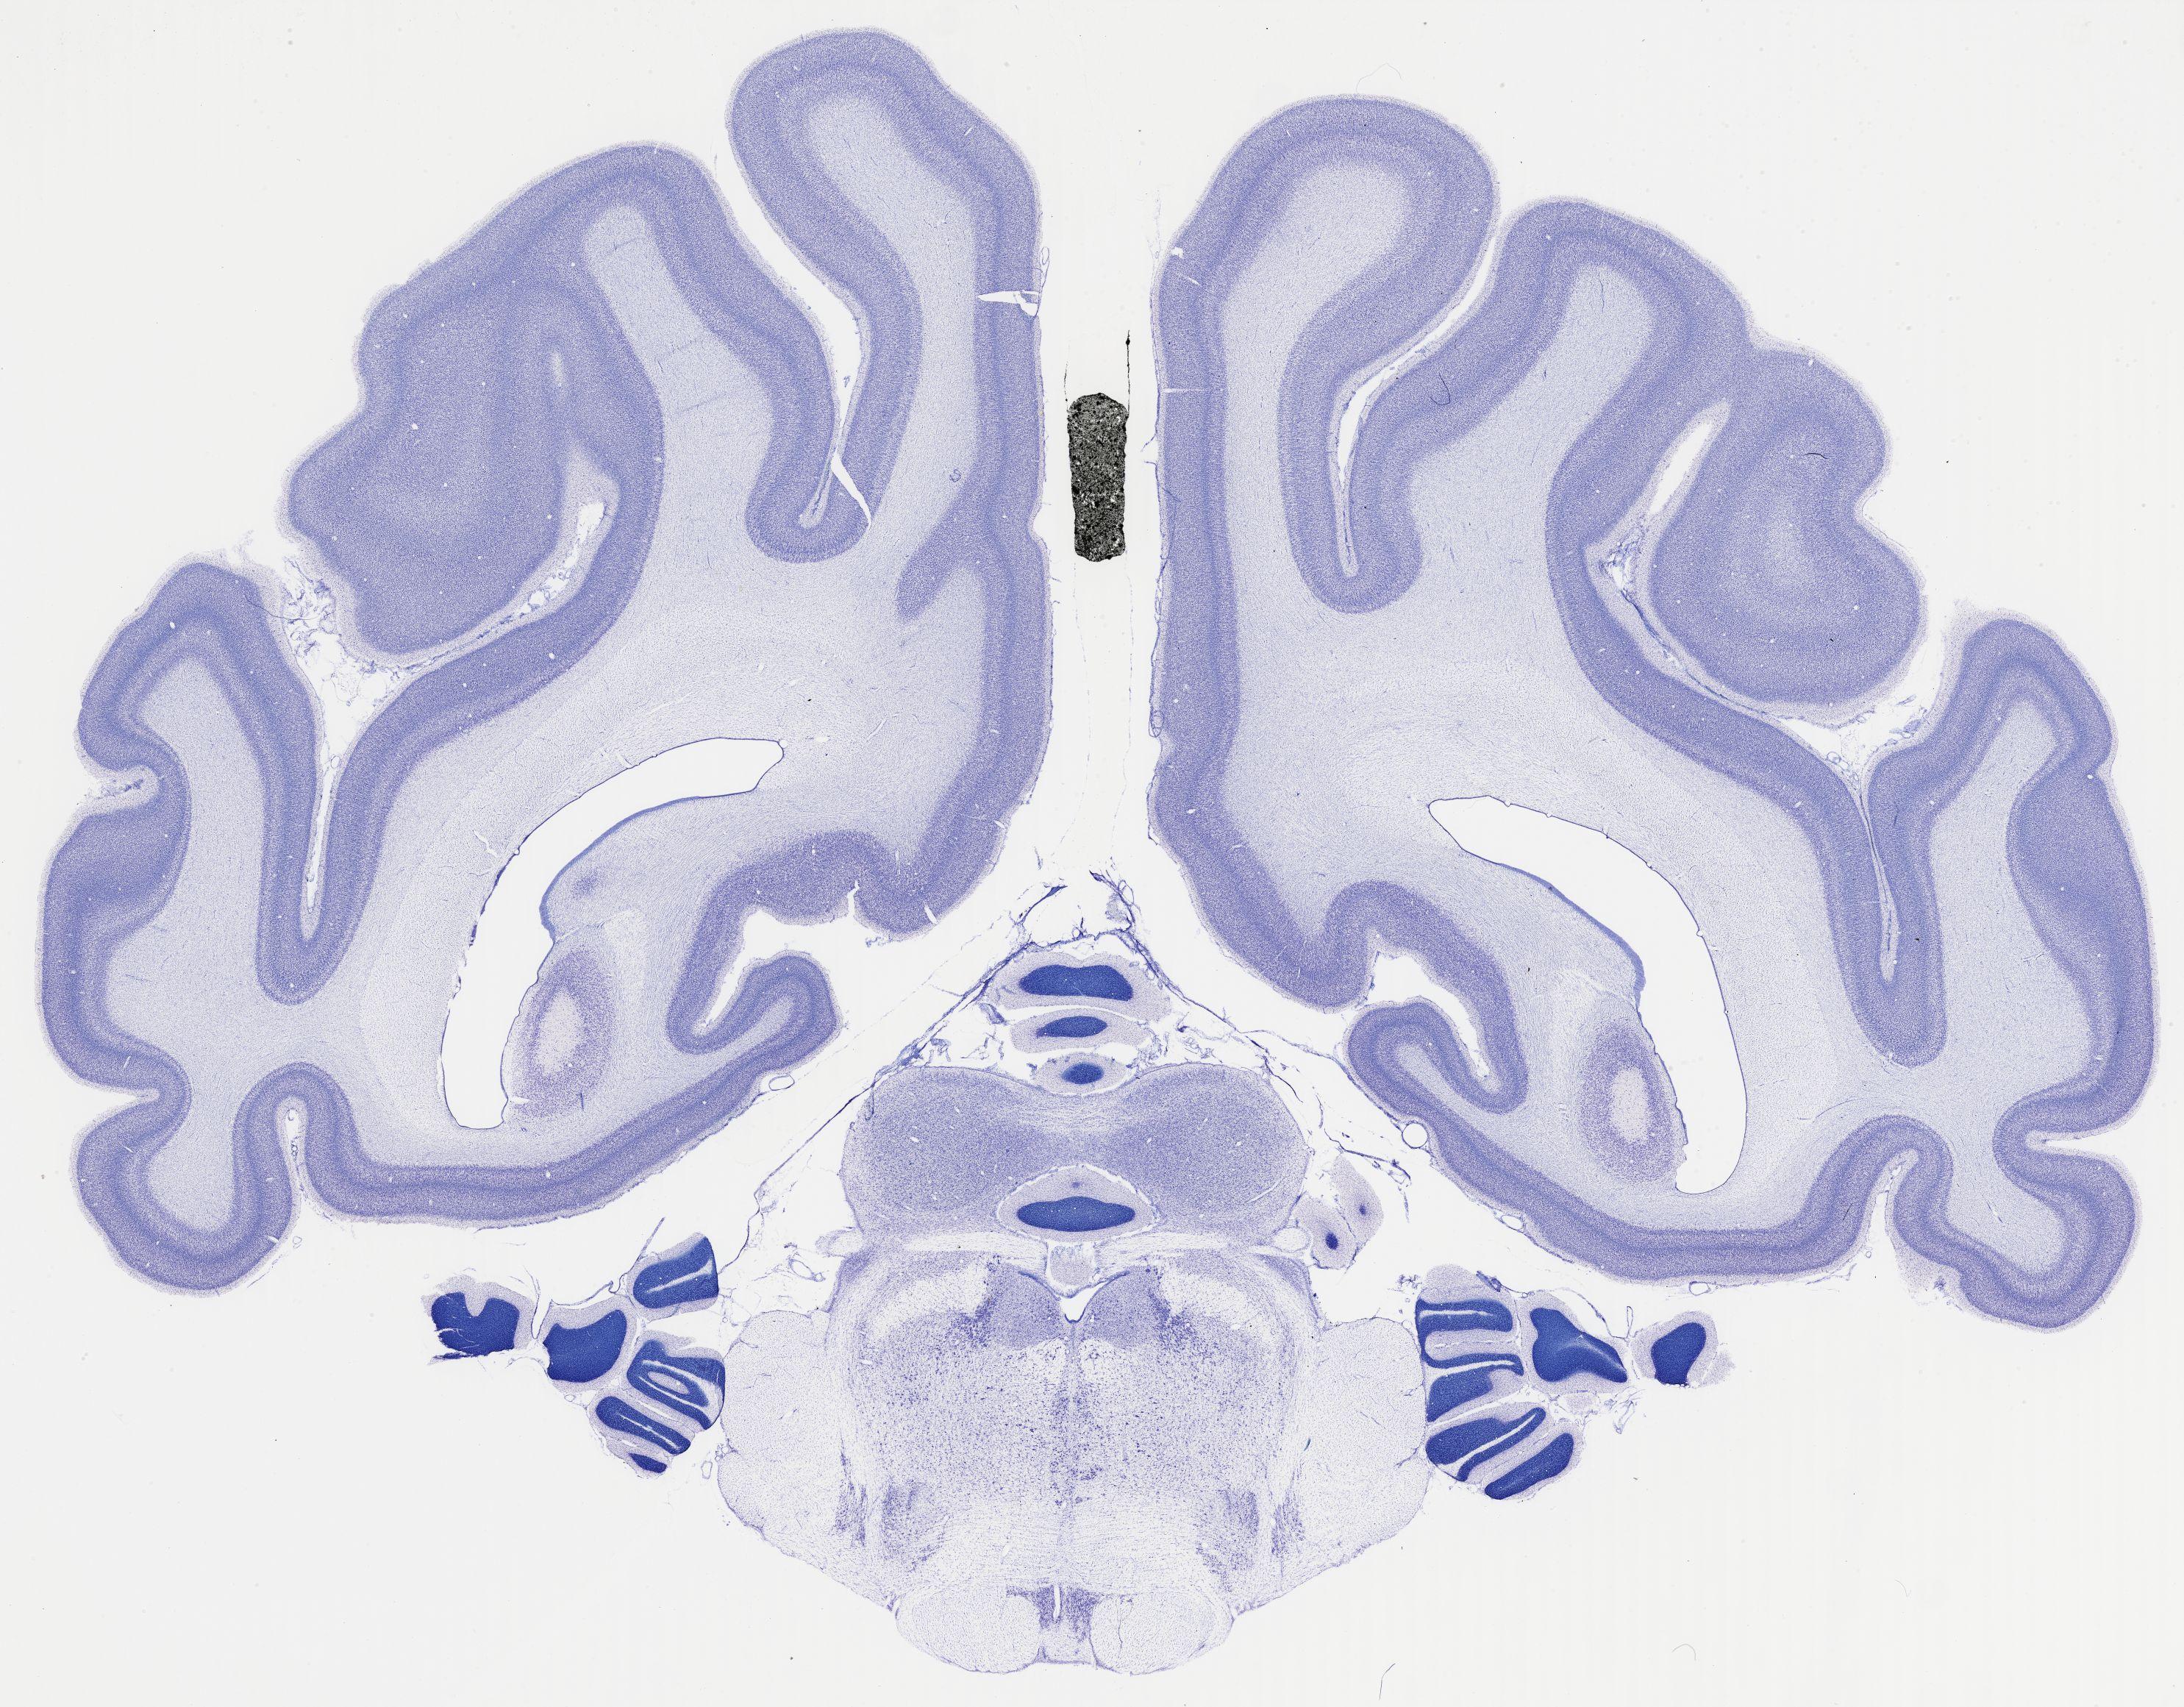

Datasets -> Chlorocebus Aethiops -> Nissl, coronal, histo, Whole-Brain, adult

[ Metadata ]   ·   Source: NeuroScience Associates

thumbnail

521